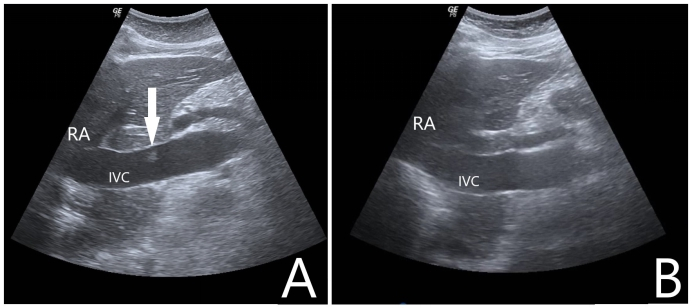

1 一般资料病例1:女性,68岁,农民,既往有“高血压病”“扩张型心肌病”“左束支传导阻滞”史,未规律诊治。主诉“突发意识不清1.5 h”于2021-02-07入院。入急诊时心搏呼吸未闻及,予高级生命支持,心电监护提示室颤,除颤治疗无效,征得家属同意后行机械按压下ECMO支持。超声引导下V-A模式上机,ECMO参数设定:转速3 500 r/min,流速3.3 L/min,吸入氧浓度(FiO2) 100%,气流量3 L/min。ECMO成功转机后停止胸外按压,患者出现ROSC,复查床旁心电图提示“右束支传导阻滞”。患者转运至介入室行经皮冠脉造影提示左右冠主干及各支未见病变,行头颅CT、胸腹主动脉CTA检查未见明显异常,考虑本次系扩张型心肌病合并双侧束支传导阻滞引起心搏骤停,予安置临时起搏器。ECMO上机后共使用肝素3 000 U,返回急诊ICU后给予全身肝素化抗凝,每2 h监测一次活化部分促凝血酶原激酶时间(activated partial thromboplastin time,APTT),目标APTT维持在60~80 s。入院后第1天患者出现消化道出血、穿刺处大量渗血、ECMO流量不稳定,血常规提示血红蛋白进行性下降,心脏彩超检查提示左室腔55 mm,左心室射血分数(left ventricular ejection fraction,LVEF):21%,左室壁运动普遍弥漫性减弱,给予输红细胞悬液6 U、新鲜冰冻血浆2 900 mL并调整肝素抗凝强度使得APTT维持在50~60 s。入院后第3天患者消化道出血及穿刺处渗血好转,停血管活性药物,未再发恶性心律失常。入院后第4天撤除ECMO,撤机前ECMO参数设定:转速2 250 r/min,流速1.8 L/min,吸入氧浓度40%,气流量3 L/min。入院后第5天心脏彩超提示LVEF:39%,同时发现下腔静脉距离右心房入口4 cm左右有附壁血栓形成,长约1.09 cm,宽0.5 cm,随血流飘动(如图 1A所示),筛查下肢其他部位未见明显血栓形成,遂给予依诺肝素钠100 IU/kg皮下注射每12 h一次治疗。入院后第7天行超声检查下腔静脉未见明显异常回声(如图 1B所示),考虑抗凝治疗后血栓消失。住院期间患者未出现过下腔静脉综合征或肺栓塞的症状或体征。经过后期的心肺康复治疗患者于2021-03-11出院,意识水平恢复正常,遗留双下肢肌力下降。

| A:箭头显示超声下在下腔静脉处附壁漂浮的血栓;B:经治疗后超声在下腔静脉未见明显异常回声;RA:右心房,IVC:下腔静脉 图 1 撤离ECMO 1 d后行下腔静脉超声检查 |